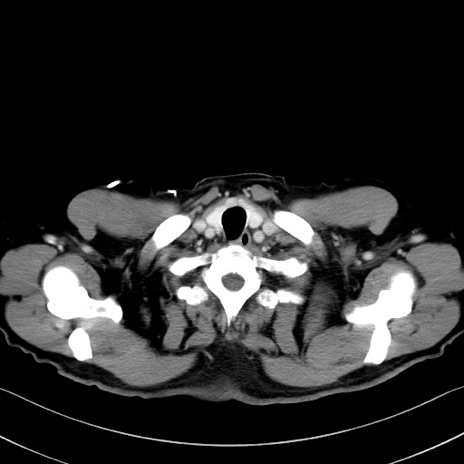

冠状断像